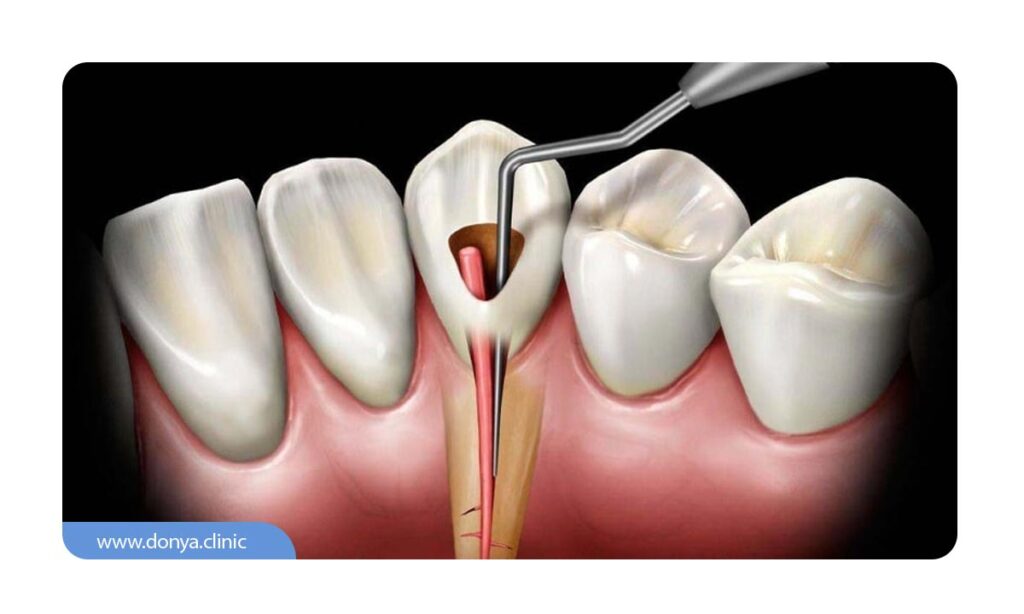

طبق گفته ویکی پدیا: «عصب کِشی (پالپِکتومی) اعمالی است که در طی آن مواد عفونی و عصب موجود در مغز دندان برداشته می شوند تا دندان از آسیب میکروب ها در آینده در امان باشد.» این مشکل معمولا در اثر پوسیدگی شدید، ضربه به دندان یا ترک های عمیق اتفاق می افتد. در عصب کشی، دندانپزشک با دقت محتوای داخلی ریشه را خارج کرده، فضای درون کانال ها را تمیز و ضد عفونی می کند و سپس آن را با مواد مخصوص پر می نماید. هدف اصلی از این درمان، جلوگیری از گسترش عفونت و حفظ دندانی است که در غیر این صورت باید کشیده می شد. برخلاف باور عموم، عصب کشی نه تنها دردناک نیست، بلکه راهی برای رهایی از درد طاقت فرسای دندان است.

عصب کشی زمانی انجام می شود که بافت زنده داخل دندان یا همان پالپ، به علت عواملی مثل پوسیدگی عمیق، ترک یا شکستگی، ضربه ناگهانی یا عفونت شدید، آسیب دیده یا مرده باشد. در این شرایط، باکتری ها به عمق دندان نفوذ می کنند و باعث درد، التهاب و در موارد پیشرفته تر، آبسه یا تورم در لثه می شوند. در صورت عدم درمان، این عفونت می تواند به بافت های اطراف دندان سرایت کرده و حتی منجر به از دست رفتن دندان شود. عصب کشی تنها راه حفظ دندان در چنین شرایطی است.

هرچه دندانی کانال های بیشتری داشته باشد، فرآیند عصب کشی دندان پیچیده تر، زمان برتر و طبیعتا پرهزینه تر می شود. به عنوان مثال، عصب کشی تک کاناله در دندان های جلویی معمولا ساده تر و سریع تر است، اما عصب کشی چهار کاناله در دندان های آسیای بزرگ، نیاز به تخصص بالاتر، ابزار دقیق تر و زمان بیشتر دارد. همچنین، هر کانال باید جداگانه تمیز، ضدعفونی و پر شود، بنابراین هزینه نهایی بسته به تعداد کانال ها و سختی دسترسی به آن ها (به خصوص در دندان های عقل) تغییر می کند. در برخی موارد خاص، ممکن است نیاز به عصب کشی مجدد باشد که به دلیل پیچیدگی های بیشتر، هزینه و زمان بیشتری نیز می طلبد.

یکی از تفاوت های اصلی در عصب کشی دندان جلو و عقب، تعداد کانال های ریشه و دسترسی به آن هاست. دندان های جلویی معمولا فقط یک ریشه و یک کانال دارند، بنابراین عصب کشی آن ها ساده تر، سریع تر و کم هزینه تر است. از طرفی، این دندان ها بیشتر در معرض آسیب ناشی از ضربه یا ترک هستند.

اما دندان های آسیای عقب (به خصوص در فک بالا) معمولا چندین ریشه و کانال دارند و دسترسی به آن ها برای دندانپزشک دشوارتر است. به همین دلیل، عصب کشی دندان های عقب معمولا نیاز به تجهیزات پیشرفته تر، زمان بیشتر و در برخی موارد تخصص اندودنتیست دارد. از نظر هزینه هم، این تفاوت چشمگیر است.